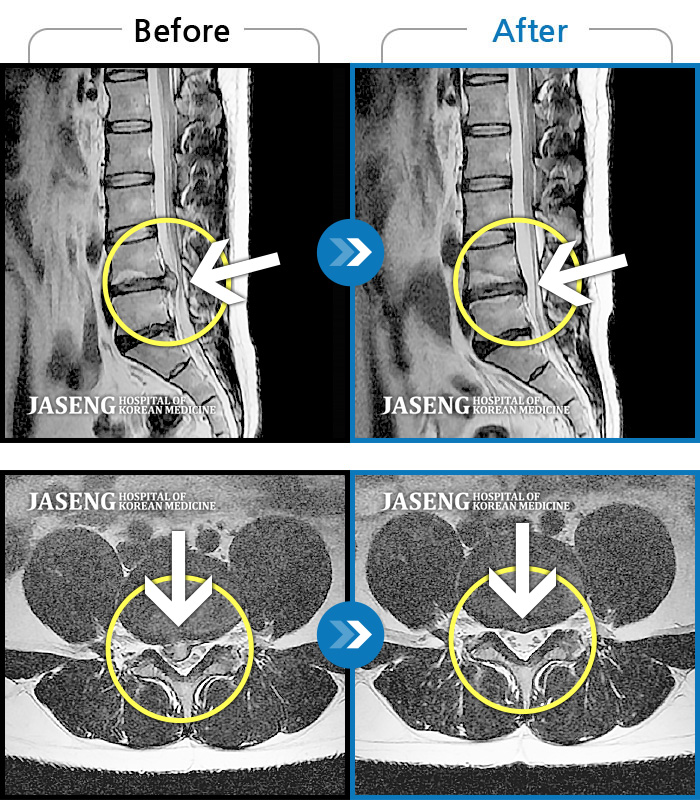

25년 1월 허리통증이 시작되고 잠을 잘수도없고 걸을 수 없을만큼의 상태가 되었을때 다시 김태용 원장님께 진료를 받고 예전 허리수술의(4번5번)(3번4번)디스크탈출증 재발과 협착증의 진단을 받고 지금까지 기나긴 여정의 입원 치료를 하며 곧 퇴원을 앞두고 있습니다.